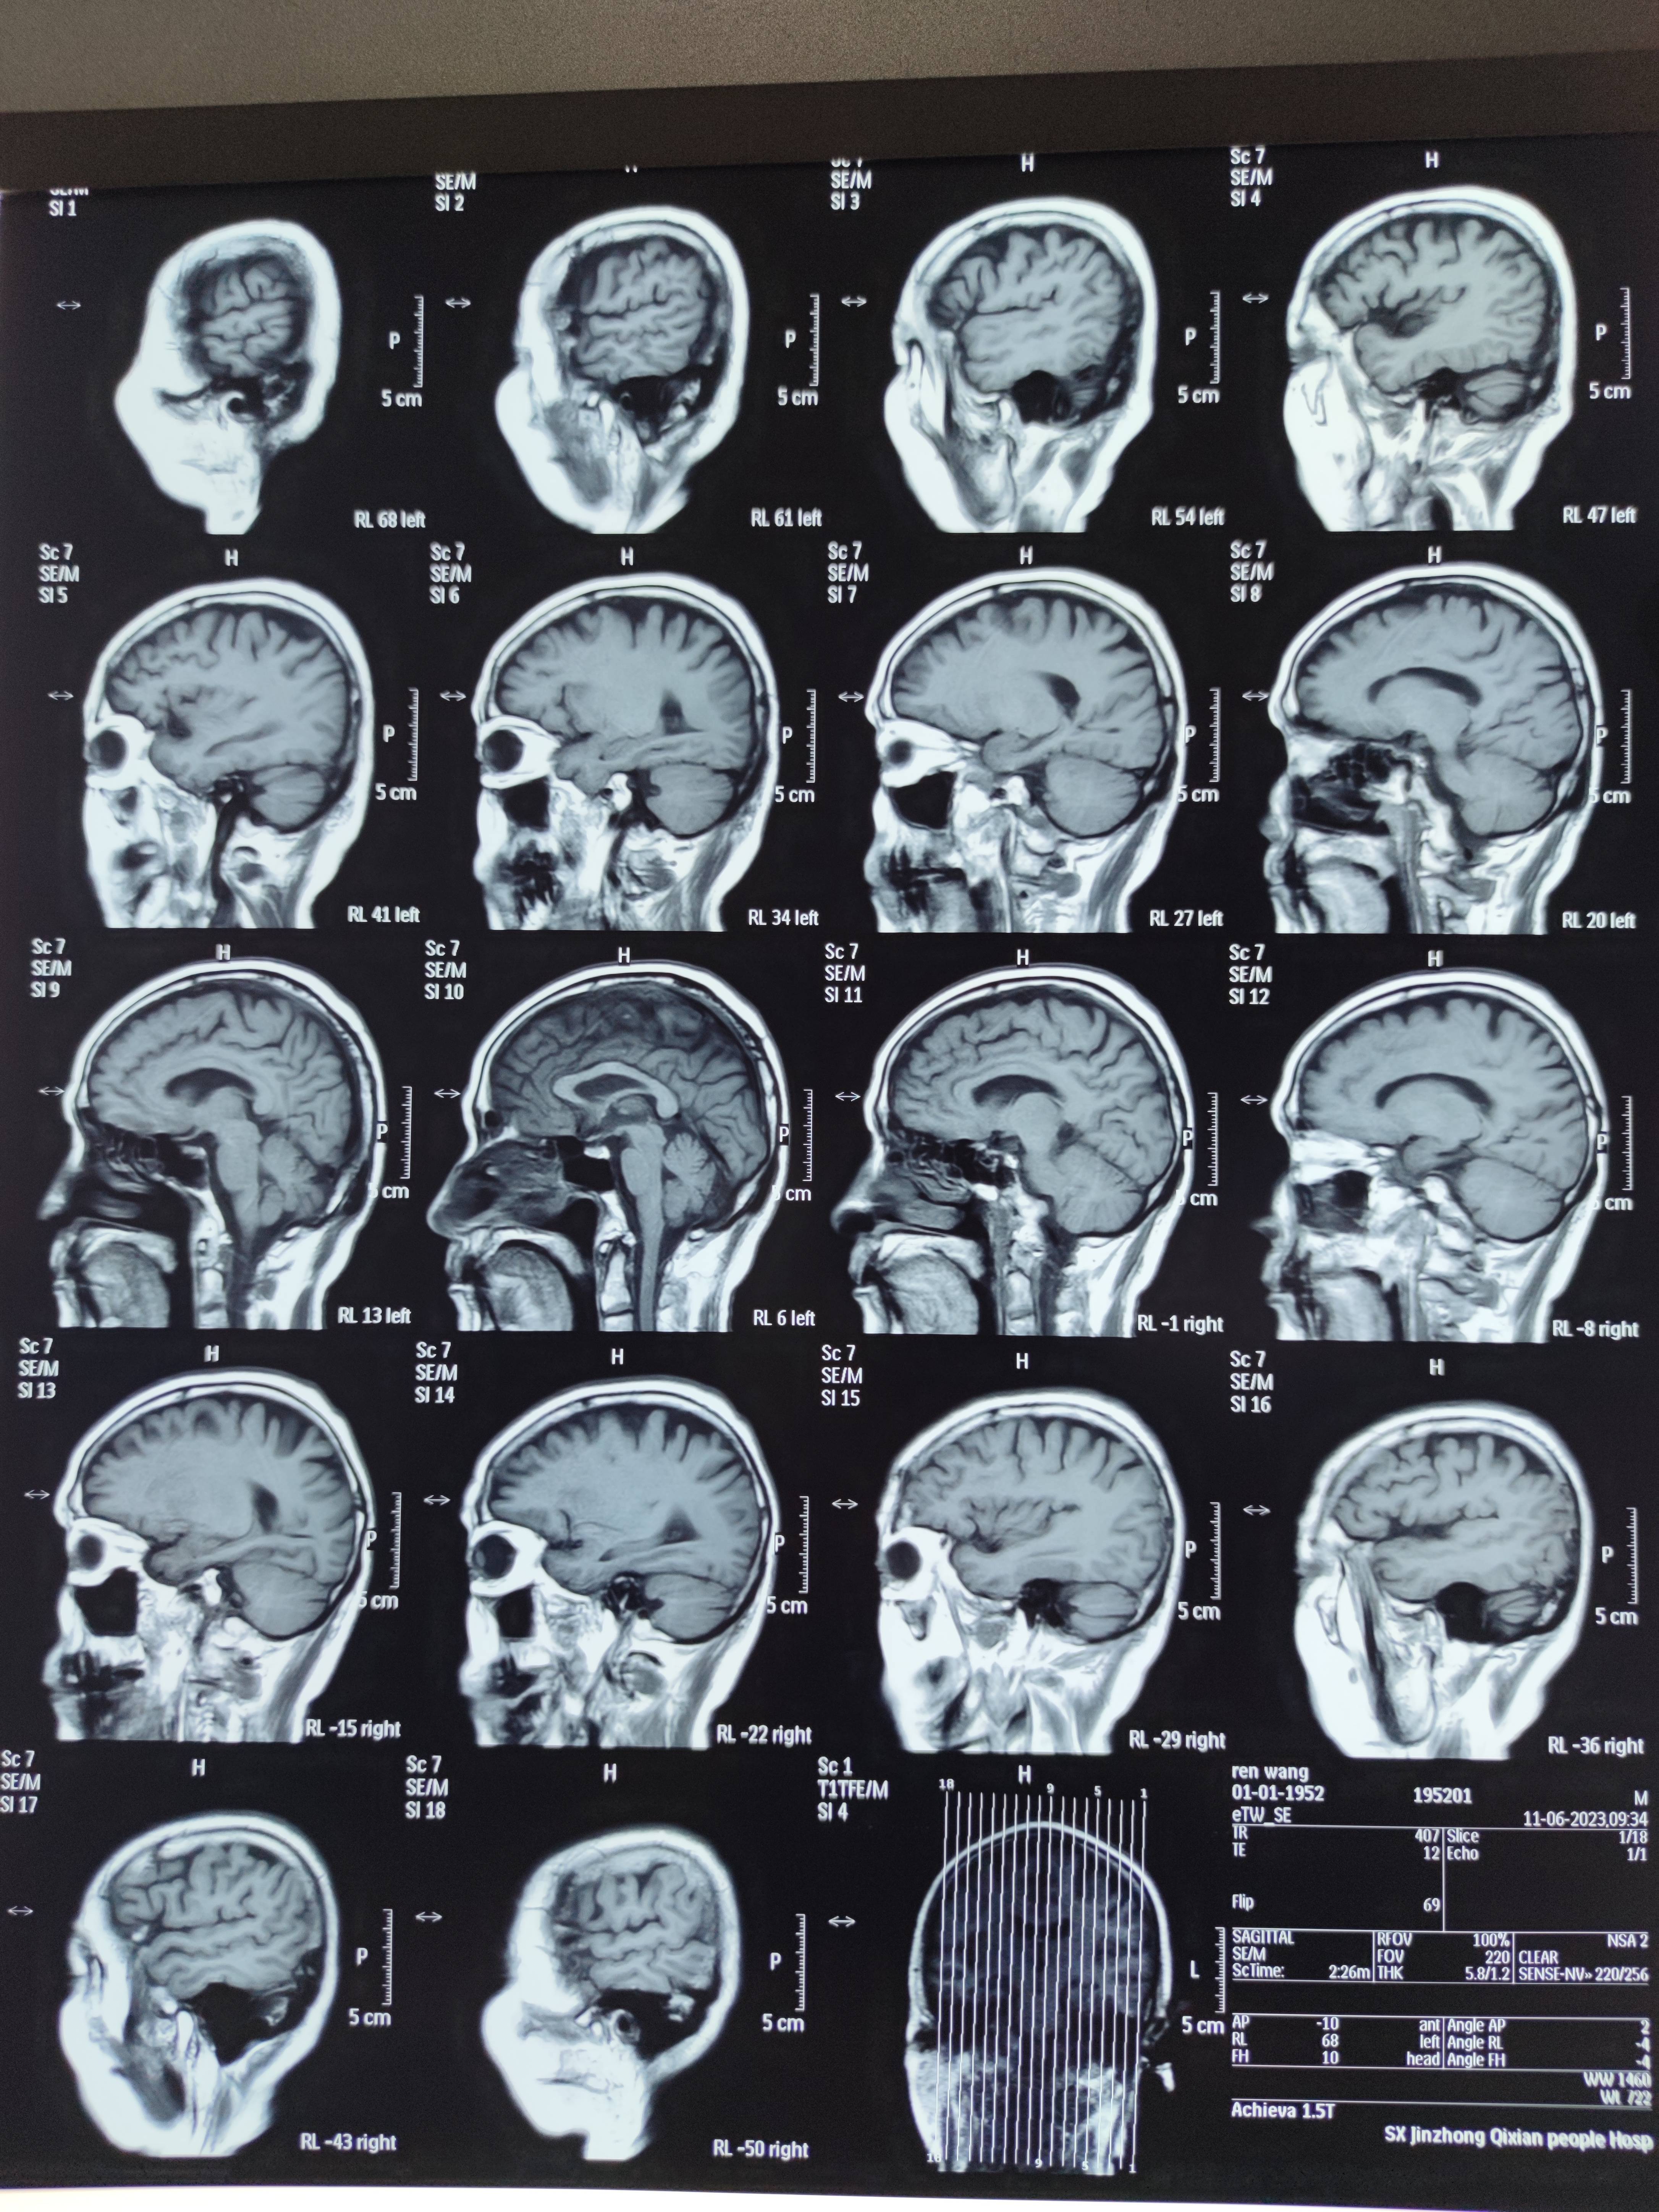

四月份癌胚抗原还是5.6,这个月到8了,持续升高。做了核磁增强,左侧桥小脑角哪有个地方不确定。肝脏核磁平扫弥散有两个点状高信号,转移也排不了,胃肠镜正常,左颈部有个变圆的淋巴结,保险点是不该加个化疗药了?咨询了陈波主任,等结果的吧!图片